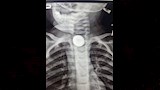

نجح فريق طبي بمستشفى أطفال بنها بقيادة الدكتور محمد متولي، ومشاركة الدكتور عمرو عبد الملك استشاري جراحة الأطفال، في إجراء عملية دقيقة لاستخراج بطارية من مريء طفل يبلغ من العمر عامًا وأربعة أشهر، في تدخل عاجل أنقذ حياته من مضاعفات خطيرة.

وأشار المستشفى في بيان له، إلى أن الطفل وصل إلى الطوارئ وهو يعاني من صعوبة شديدة في البلع وآلام مستمرة بالصدر، موضحا أن الفحوصات العاجلة كشفت وجود بطارية صغيرة مستقرة في المريء.

وأضاف المستشفى، أن الفريق الطبي تدخل فورًا باستخدام المنظار الجراحي، حيث تم استخراج البطارية بنجاح دون أي مضاعفات، مؤكدًة أن التدخل السريع والتقنيات الحديثة كانا عاملين حاسمين في إنقاذ حياة الطفل.